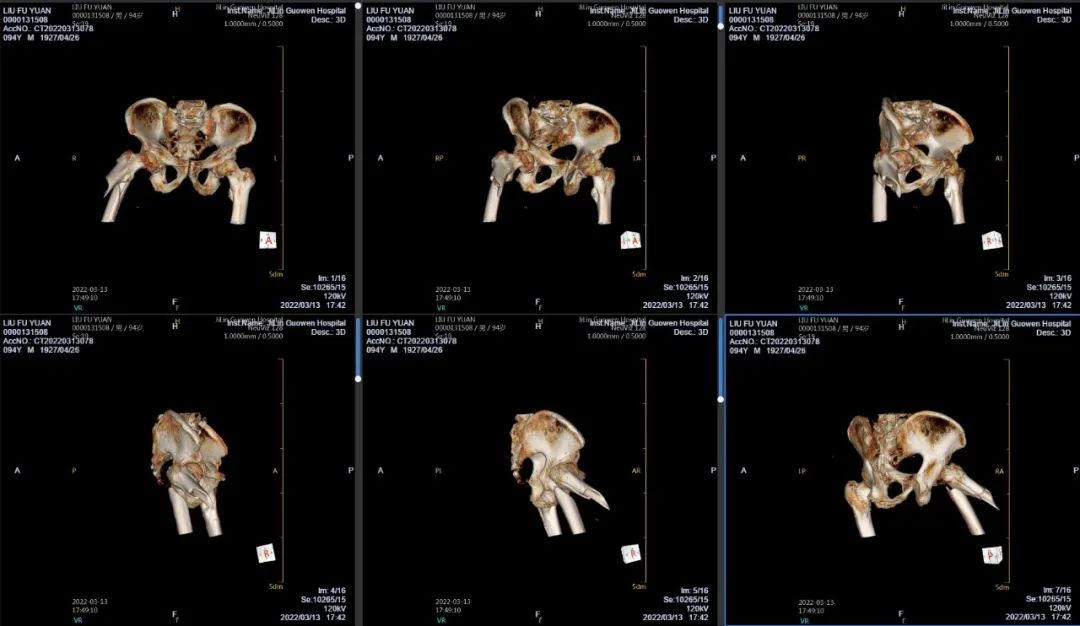

3月13日伴著急促的腳步聲、轆轆的車輪聲,夾雜著患者痛苦的呻吟聲,一位94歲的高齡老人被急診科醫(yī)護(hù)人員緊急送至骨科療區(qū)。這是怎么回事?呂國褔主任帶著值班醫(yī)生在做好防護(hù)措施后,第一時間來到患者病床前,經(jīng)急診科醫(yī)生診斷告知為 “股骨近端粉碎性骨折”,患者右大腿近端嚴(yán)重畸形,骨折端已經(jīng)刺穿前方肌肉直達(dá)皮下,局部皮膚高高隆起,局部皮膚有挫傷灶,呈青紫色,皮膚變薄,皮膚外可明顯觸及骨折斷端,右股骨X線片示:右股骨近端粉碎性骨折,斷端移位明顯,斷端銳利,近斷端位于前方皮膚下,局部皮膚隆起。患者疼痛劇烈,痛苦難耐,測生命體征:血壓:220/110mmHg。

骨科醫(yī)生緊急會診評估,考慮到患者高齡,近百歲老人、同時患有高血壓3級(極高危),如急診手術(shù)、需要進(jìn)行全身麻醉,手術(shù)存在相當(dāng)大風(fēng)險;如不做手術(shù),骨折端已嵌于肌肉組織內(nèi)很難通過牽引復(fù)位,患者疼痛、肌肉組織收縮,很容易將皮膚刺破,變成開放性骨折,增加患者痛苦,影響預(yù)后。

面對如此高齡患者,為降低手術(shù)難度及麻醉風(fēng)險。同時考慮到患者疼痛劇烈,無法配合腰麻,需要全麻。吉林國文醫(yī)院的專家團(tuán)隊(duì)們決定采取“有限切開,髓內(nèi)釘內(nèi)固定術(shù)”,該手術(shù)創(chuàng)傷小,風(fēng)險低,術(shù)后有利于患者恢復(fù)。在麻醉科、心血管內(nèi)科團(tuán)隊(duì)的保駕下,于當(dāng)日夜間緊急為老人家實(shí)施手術(shù),手術(shù)歷時1個多小時。為能及時應(yīng)對患者出現(xiàn)術(shù)中血壓波動大的風(fēng)險,麻醉科劉桂穎、程志超兩位主任及麻醉科值班醫(yī)生一直陪伴在老人身邊,監(jiān)護(hù)手術(shù)整個過程。